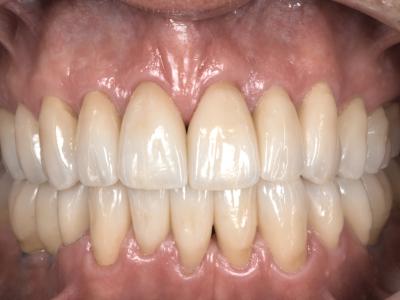

En fin de traitement pré-prothétique, une analyse globale de la nouvelle situation est réalisée pour élaborer un plan de traitement prothétique. Bien que l’occlusion obtenue soit stable et fonctionnelle, le sourire du patient reste disgracieux. La présence de trous noirs interproximaux, des anomalies de proportions, de nombreux composites de collet ainsi que quelques mylolyses restent préjudiciables au niveau esthétique.

Avant d’aller plus loin dans la réflexion esthétique, le calage postérieur est finalisé à l’aide de couronnes définitives sur les implants 36-37-46, et de composites directs sur 27-26-17-36-37-47. 38, sans utilité fonctionnelle, est avulsée afin de faciliter l’accès au nettoyage de 37.

Pour finaliser le plan de traitement, une simulation numérique du projet esthétique est réalisée, à partir d’une analyse photo et vidéo du sourire. La séquence vidéo assure une meilleure évaluation de la dynamique dento-labiale lors de la phonation. Elle précise également le sourire Duchenne du patient et donc le positionnement le plus haut de sa lèvre supérieure. Un wax-up, réalisé par le prothésiste à l’aide du projet virtuel, permet de le visualiser en bouche avec un mock-up. Après validation, les pièces partielles en céramiques collées sont élaborées. Du fait des récessions, les limites de préparation présentent des plages avec peu, voire pas d’émail. Une attention particulière est apportée au protocole de collage, effectué sous digue, avec un MR3 par mordançage, rinçage puis application séparée de primer et d’adhésif avant de coller avec un composite dual.